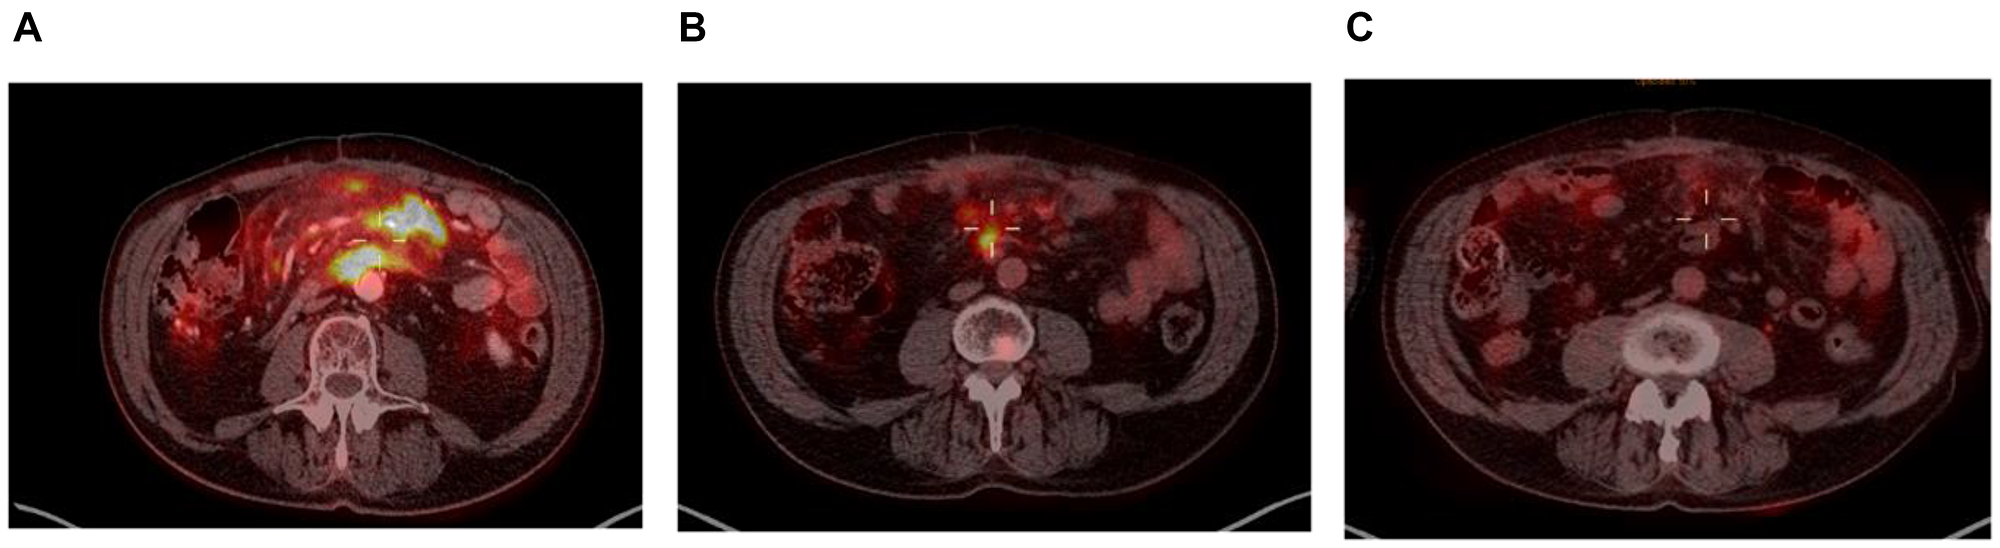

Taking a closer look at those 2 patients, both had localized disease at inclusion (Ann-Arbor stage II), and their responses to enitociclib progressively deepened over time. Partial responses were achieved after 5 and 6 months and complete metabolic responses (CMR) at 7 and 8 months from the first dose received (Figures 1 and 2). These patients stopped treatment (as a result of the COVID-19 pandemic during which follow-up became more difficult) after 20 and 36 months in complete remission, respectively. And after 6.4 and 4.8 years, their CMRs continue to be sustained as of today. These findings are indicative of the antitumor activity of this new CDK9 inhibitor against HGBL. However, it requires time to achieve this effect, likely because the drug’s mechanism of action requires time to fully inhibit the production of short-lived proteins and thus induce clinical responses.

Figure 2: PET scan at screening (A), at 6 months (B) and at 7 months (C).